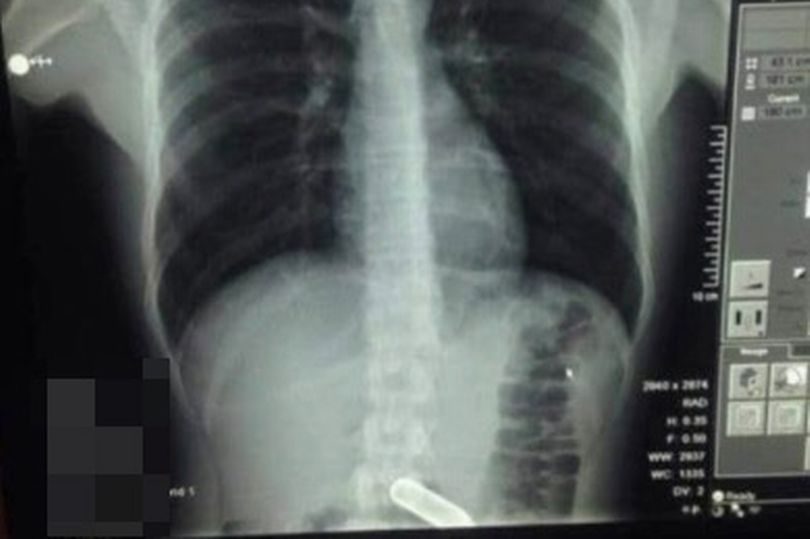

У клініці лікарі повідомили, що ніколи раніше не стикалися з таким випадком. Дослідження показали, що металевий предмет застряг на дні живота пацієнта.

Газовий балончик довелося витягувати шляхом хірургічної операції. При цьому була небезпека, що вибухонебезпечний предмет розірветься прямо всередині пацієнта. На щастя, лікарям вдалося витягти балончик, не викликавши смертельного вибуху.